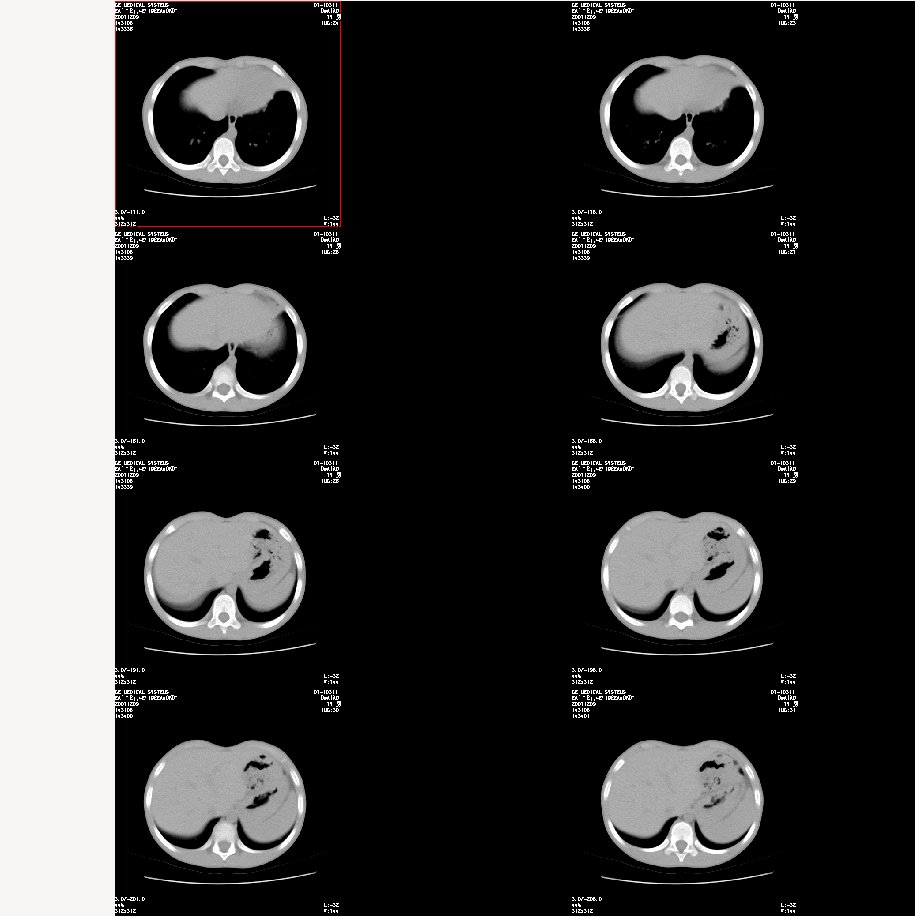

标题: 纵隔窗:

图像太小了,不好看,左肺出血、感染性病变?

双肺感染性病变——结核可能性大!

首先考虑肺内炎症。

支持肺炎,建议严格抗炎治疗后复查。

炎症应该有,排除一下有没有支扩吧

左肺上叶上舌段不张实变,建议纤支镜检查

左肺炎症,是否为过敏性。

支持 肺发育不全伴感染与支气管扩张